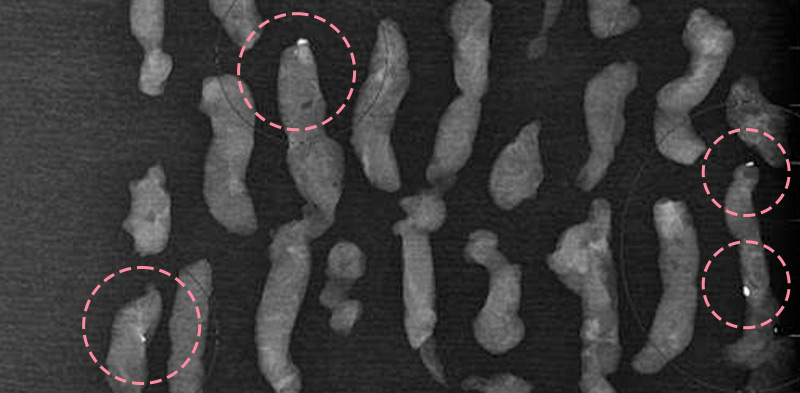

유방 양성 종양은 한 개만 나타나는 것이 아니라 동시다발적으로 생겨나기도 합니다.

여러 개의 양성 종양 제거는 정상적인 유방 조직을 온전히 보전할 수 있도록 섬세한 시술이 필요합니다.

한송이 원장은 다발성 종양 제거에 대한 풍부한 경험을 토대로, 무리 없이 맘모톰 조직검사 및 제거를 진행했습니다.

맘모톰시술 6개월 후 유방초음파 검사 시행 결과 종양이 깨끗하게 제거됨을 확인했으며, 약간의 반흔 조직이 남았으나 시간이 지나면서 대부분 사라지기 때문에 좋은 예후가 기대되었습니다.